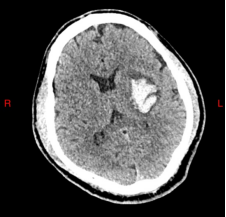

患者何先生(化名)因突发右侧偏瘫、失语紧急入院,CT显示其左侧基底节区脑出血量达20ml,病情危重。传统手术存在“盲穿”风险高、创伤大等问题,而红会医院神经外科别小华主任团队创新采用“可视导管+C臂CT导航”技术,实现全程可视化操作。

术前CT:清晰显示左侧基底节区20ml血肿

术中,团队通过导管内置高清摄像头精准避开血管,直达血肿中心,结合C臂CT实时导航动态调整穿刺路径,误差控制在1毫米以内。手术仅耗时30分钟,术后第3天患者语言功能明显恢复,右侧肌力显著改善,血肿清除率达95%。该技术的成功应用,标志着脑出血微创治疗迈入“精准、高效、安全”的新阶段。

术后对比:血肿清除率达95%,脑组织压迫解除